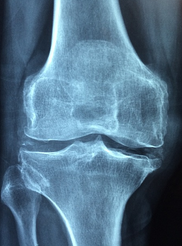

류마티스 관절염은 면역계의 기능이 이상하게 작용하여 자신의 조직을 공격하는 자가면역 질환입니다. 면역계가 실수로 인식한 본래의 조직에 대한 자체 면역 반응이 발생하며, 이로 인해 염증이 유발됩니다. 이 염증이 관절에 생기면, 관절 내부에 있는 연골과 뼈에 손상을 줄 수 있으며, 관절을 둘러싸고 있는 힘줄과 근육, 뼈와 연결된 힘줄 등에도 영향을 미칩니다.

- 수술 치료: 심한 경우에는 관절 치환 수술이나 인공 관절 삽입 수술 등의 수술 치료가 필요할 수 있습니다.